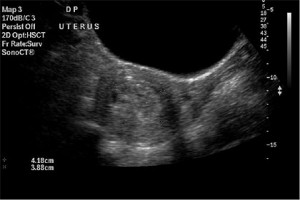

Molar Pregnancy Information. Ultrasound Included. - Ultrasoundfeminsider

Molar pregnancy information. Ultrasound included. - Ultrasoundfeminsider ultrasoundfeminsider.com